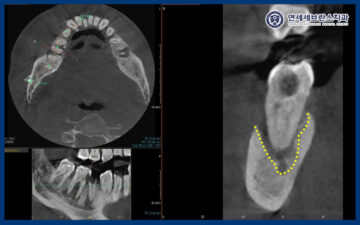

CT를 촬영하여 확인해 보았을 때,

뿌리 끝 염증이 이미 신경까지 퍼져있었으며

조금만 더 늦었으면 치아 염증이

아래턱, 얼굴 감각까지 영향을 미칠 수 있는 상황이었으며

당장 임플란트 보다는 염증 제거 및

발치 후 치유 양상 확인이 필요했습니다.